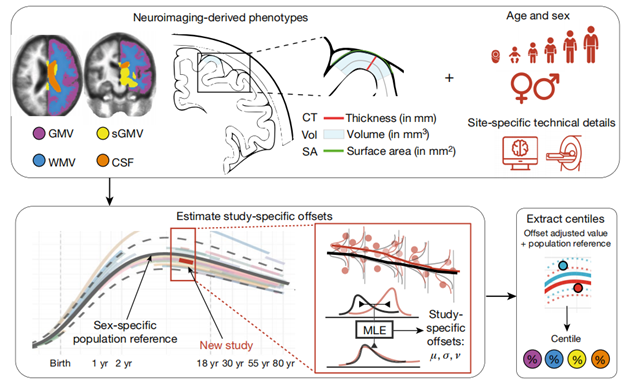

因此,如图1a所示,研究创建了一系列跨越人类整个生命周期的大脑图表,从15周大的胎儿到100岁的成年人。显示了人类大脑在生命早期迅速扩张,并随着年龄的增长而缓慢萎缩的变化过程。

正常大脑生长发育参考标准

研究人员使用基于位置、尺度和形状的广义加法模型(GAMLSS)创建了人类寿命的大脑图表。具体研究方法为,将GAMLSS模型拟合到大脑的四个主要组织体积的结构性磁共振成像数据上。如图1b-e所示,依次为,总皮质灰质体积(GMV)、总白质体积(WMV)、总皮质下灰质体积(sGMV)和总脑室脑脊液体积(脑室或CSF)。

研究人员利用大脑图表,首次确认了人类大脑的发育里程碑。例如大脑的主要组织在什么年龄阶段达到体积峰值以及大脑的特定区域何时发育成熟。使研究人员能够度量在大脑中非常早期的、快速的变化;以及随着年龄的增长,大脑长期而缓慢的衰退。研究结果发现:

新的MRI数据的局部评分

构建大脑图表的一个挑战是确定样本外MRI数据的百分位数评分。因此,研究人员仔细评估了这类“新”扫描的百分位评分的可靠性和效度。对于每项新的MRI研究,使用最大似然来计算与标准轨迹的统计偏移。研究人员以偏移轨迹为基准评估了新研究中每个个体的百分位分数(图5)。样本外百分位数在多个测试-重测数据集中被证明是高度可靠,并且对图像处理管道的变化具有鲁棒性。

图5:脑图示意图,突出样本外百分位评分方法。